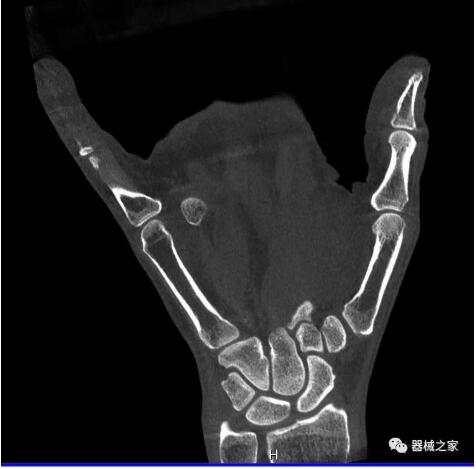

另外一款被稱為世界上最小的CT,它的重量?jī)H300磅,不僅能夠掃查足部,還可以檢查膝蓋和上肢等。

與上面介紹的CT一樣,它同樣具有輻射低、占地空間小(23*36)的特點(diǎn),隨開隨用(支持直接接入墻上的插座)。

這款CT使用非常方便,通過上下移動(dòng)保持與患者的手臂或者雙腿齊平,掃描快速,僅需要30秒左右就可以完成掃查。

以上介紹的CT均來自國(guó)外同一家公司,這些CT均配置了可視化軟件,可以進(jìn)行切片、3D重建以及大型CT附帶的所有典型的操作功能。

以下是這些“特立獨(dú)行”的CT所拍出來的圖像: